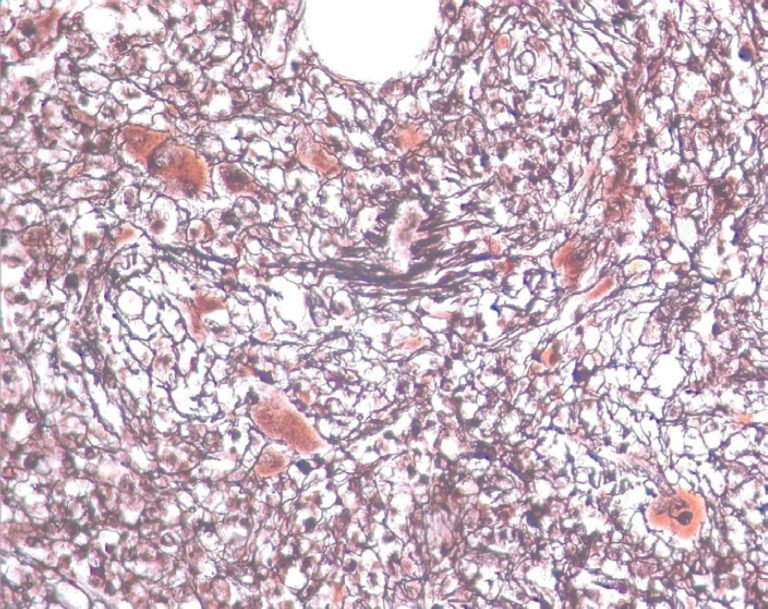

Mielofibrose acentuada, evidenciada por coloração específica (impregnação pela prata), mostrando megariócitos distorcidos de permeio a traves espessadas de reticulina

Mielofibrose acentuada, evidenciada por coloração específica (impregnação pela prata), mostrando megariócitos distorcidos de permeio a traves espessadas de reticulina